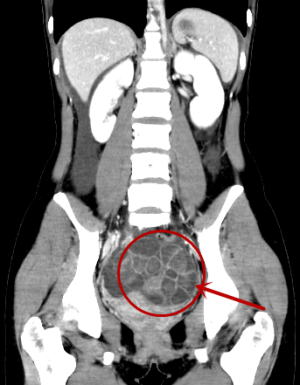

两周前的一天,姚景江在二审CT影像报告时,读到了一份“少见”的CT影像。患者是一名20岁的高校女学生,因为腹痛腹泻,她来到我院看急诊内科。医生确认她无畏寒发热,无胸闷胸痛,并否认怀孕后,怀疑可能是急性消化道疾病,建议她做一个全腹部三维螺旋CT增强扫描。CT影像冠状位重建显示腹腔大量腹水并盆腔内多发囊性病变类似肥皂泡改变。

阅片诊断医生给出的报告,考虑多囊卵巢或多发巧克力囊肿(待排查),建议结合临床相关检查确认。但是姚景江审核报告时,第一眼看到影像却感到了疑惑,这和他以往看到的多囊卵巢或巧克力囊肿的影像有区别。这名患者盆腔内围绕卵巢的囊性病变肥皂泡形状比较大,多数超过了一公分。姚景江解释,多囊卵巢的影像多是盆腔内围着卵巢排列有一圈圈整齐的囊性病变,是小的泡泡形状,不会大于一公分;而巧克力囊肿的影像是盆腔内卵巢处出现一个母囊带着许多子囊状的病变,泡泡形状的大小可辨识主病灶,且巧克力囊肿是子宫内膜异位症的一种情况,可引起每月周期性的出血,使卵巢增大形成内含陈旧性积血的囊肿,从影像上看囊腔的密度是不均衡的。而这一份CT影像均无法找到佐证多囊卵巢或巧克力囊肿的“有力证据”。

为了揪出影像中病变的“元凶”。姚景江耐心查看,仔细核对,并查阅了大量文献,在一篇核心期刊中找到类似这种盆腔内多发囊性病变的影像报告,提示卵巢过度刺激综合症,文中的患者是因做试管婴儿,使用促排卵的药物,导致雌激素水平异常升高。可是这名患者只有20岁,又是学生,既没有特殊病史,也没有怀孕,怎么会有大幅度的雌激素波动?为了弄清楚疑问,姚景江与患者取得联系,询问其近期的生活、吃食以及药物使用情况等。姚景江向患者说明了病情的复杂性和严重性,如果病变继续发展,卵巢会遭受不可逆的伤害,甚至会危及生命。最后,患者才支支吾吾地告诉姚景江,她听信了中介的诱惑,打了十几天的排卵针,用卵子换取高额报酬。得知真相后,姚景江劝说患者马上停止这种“捐卵”的行为,到妇科接受治疗。这位年轻的患者十分后悔,表示会停止自己的错误行为,去医院接受治疗。电话结束时,患者真诚地感谢姚景江,谢谢他能对自己病情“锲而不舍”的追查。